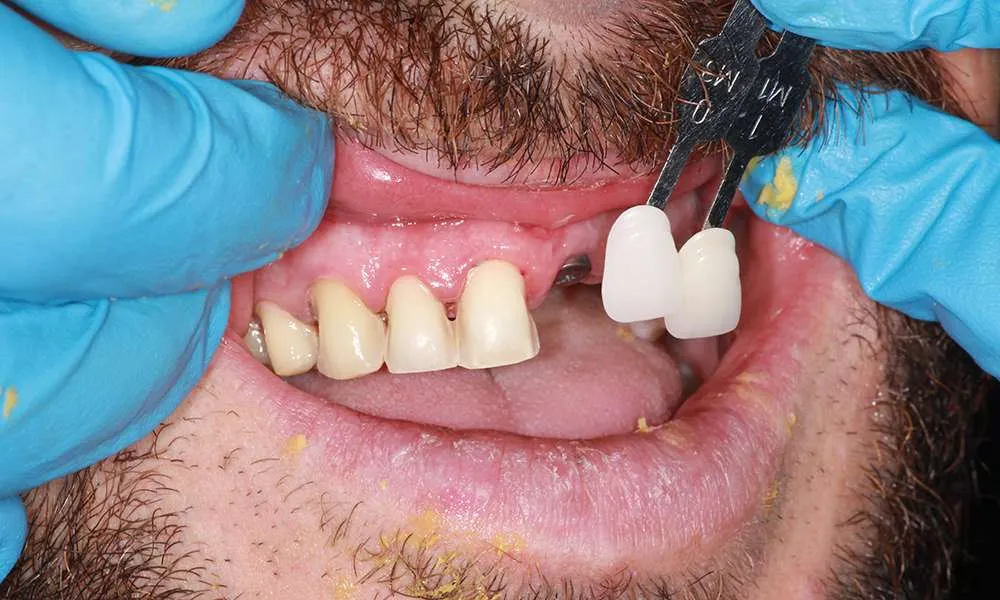

The process of getting ultra-thin veneers typically involves several steps. First, during the initial consultation, we will discuss your goals and take impressions and photographs of your teeth. Next, we will minimally prepare your teeth generally less than 0.5mm of preparation (sometimes little or no preparation is needed depending on the design). Then you'll leave with a 'trial smile' and temporary veneers in place, after which we'll have a follow-up appointment the next day for final evaluation of your temporary veneers for tweaks and fitting to help guide the lab to your custom smile. Your veneers are finally crafted in a premier dental lab. Finally you'll return to the office where your custom, ultra-thin veneers are bonded to your teeth using biocompatible materials. The entire process usually takes one to four weeks from start to finish depending on the lab and complexity of the case.

Ultra-thin veneers are crafted from high-quality materials that closely resemble the look and feel of natural teeth. The translucency and texture of these veneers mimic the appearance of real enamel, ensuring that your smile looks natural and aesthetically pleasing. Each veneer is custom-made to match the color, shape, and size of your existing teeth, blending seamlessly with your natural smile. This attention to detail ensures that your veneers are virtually indistinguishable from your natural teeth, providing you with a flawless, beautiful smile.